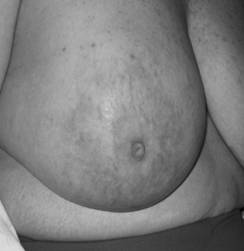

In October 2007, almost a year after her initial ovarian cancer diagnosis, the patient reported the new-onset of right breast edema. Although she had been previously followed for the right axillary lymphadenopathy, she had recently noticed an increase in erythema, thickness, and warmth of the skin of her right breast [Fig 1, 2]. She was treated with a 10-day course of antibiotics, with no change in symptoms. She then underwent an ultrasound of her breast that showed an ill-defined hypoechoic area in the right upper outer quadrant with multiple enlarged lymph nodes. A subsequent mammogram showed scattered fibroglandular densities and an area of architectural distortion with a few small punctate calcifications. Her gynecologic oncologist performed a fine-needle aspiration of the breast, which showed cells consistent with adenocarcinoma. She then underwent a second bilateral breast MRI, which confirmed the presence of an area of heterogeneous enhancement measuring 8 x 4 cm, highly suggestive of cancer, with areas suspicious for tumoral extension to the chest wall [Fig 3, 4].

Figure 1

Picture demonstrating the inflammatory changes present on initial presentation.

Figure 2

Picture demonstrating the size discrepancy between the two breasts.